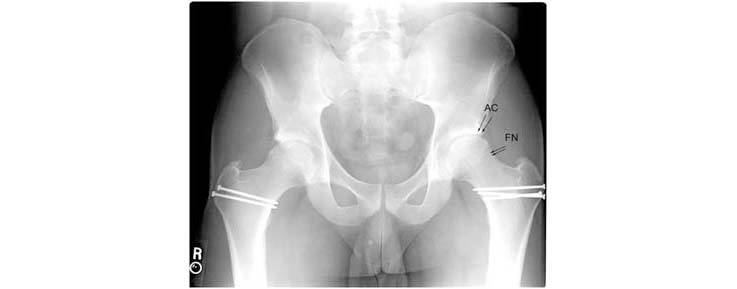

2.This is the radiograph after the patient has undergone bilateral surgical dislocations. The abnormal bone was resected on the edge of the femoral head. The edge of the acetabulum was also trimmed back to eliminate the abnormal contact.